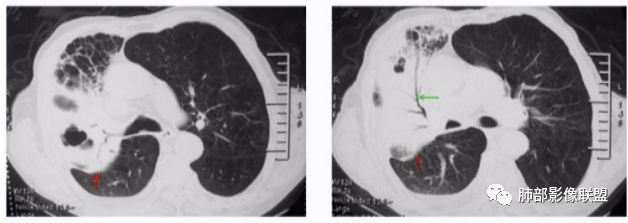

张丽红: 支原体

若晗: 支原体

最后一束散射线: 支原体

衡妈: 支原体

若晗: 结节十树芽十树雾

deng: 这个支原体了

张世晓: 支原体

青藤之凉: 支原体肺炎的影像特征相对比较明显。有支气管壁增厚、支气管扩张样改变、支气管充气征。小叶小结节,有点状或者斑片状的浸润影、有实变影,表现为树芽征、树雾气征。

青藤之凉: 临床特点:①临床轻,影像重,病程较长。②儿童和青少年发病。

影像学特点:①支气管壁增厚、支气管周围炎。②腺泡结节、树芽征、树雾征(见病例1)。③结节融合,大片实变,部分边缘收缩。④分布上较广泛 。